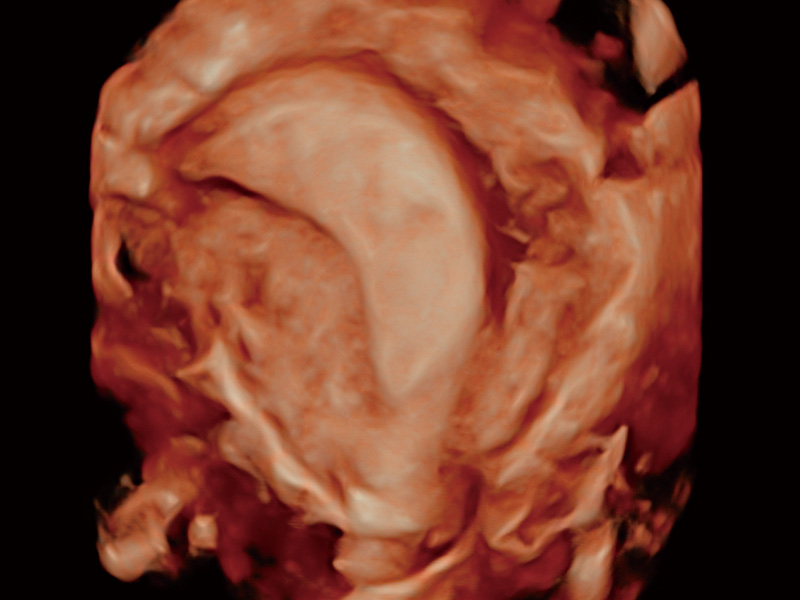

“生育问题”即关系民族复兴,也关系亿万家庭的幸福。随着婚育年龄推迟、社会压力增加等因素,越来越多人群也面临着“生不出、生不好”的问题。辅助生殖作为治疗不孕不育最有效的方法之一,也逐渐成为育儿新希望。而超声检查能为生殖需求人群的初诊评估提供宝贵的信息。 P20 Elite是新葡的京集团8814检测站匠心打造的一款生殖应用型彩超。她继承新葡的京集团8814检测站高端极光平台,突破性地将多款新型芯片及硬件模块进行整合,均衡了高端系统性能与小巧灵动机身。P20 Elite卓越的图像质量搭载专科探头,旨在为您提供全面的辅助生殖解决方案。

P20 Elite配备了丰富的生殖探头群和临床应用功能,在卵泡监测、穿刺取卵、胚胎移植、妊娠确认等领域,为生殖需求人群提供了新的临床机会,重新定义高端超声如何应用于生殖健康检查。